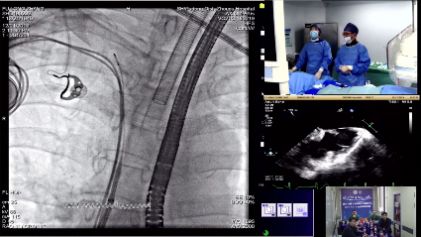

会议期间,包括3台TAVR手术和7台LAAC手术在内的手术演示在个医院的手术室进行。TAVR手术由周达新教授、潘文志教授、宁忠平教授、陈莎莎教授、武英彪教授等操作。LAAC手术由余江涛教授、宁忠平教授、赵冬冬教授、江立生教授、白元教授、张庆勇教授等进行。同时在演播室邀请多位专家进行现场点评和讨论,专家们的手术实操与学术分享内容相辅相成,为更多的医生掌握手术操作技巧提供了助益。